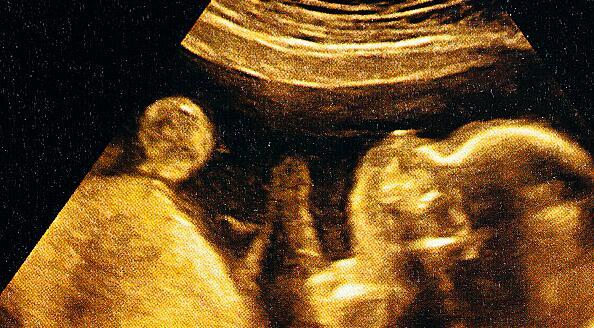

妊娠7—8周时,超声所见到胚芽有轻微的波纹状运动;

2、怀孕中期以后的胎动:

如惊跳、全身运动、孤立的上肢或下肢运动、屈伸头部、转头、转身、伸展、张口、手触脸部及打呃、打哈欠、吸吮、吞咽等。这些运动,在妊娠13—15周达最高峰,17周后逐渐减少。

3、足月后的胎动:

接近足月后,尤其是38周以后,较大幅度的全身运动更少,仅能观察到眼的运动、张口、手的活动及呼吸运动等。